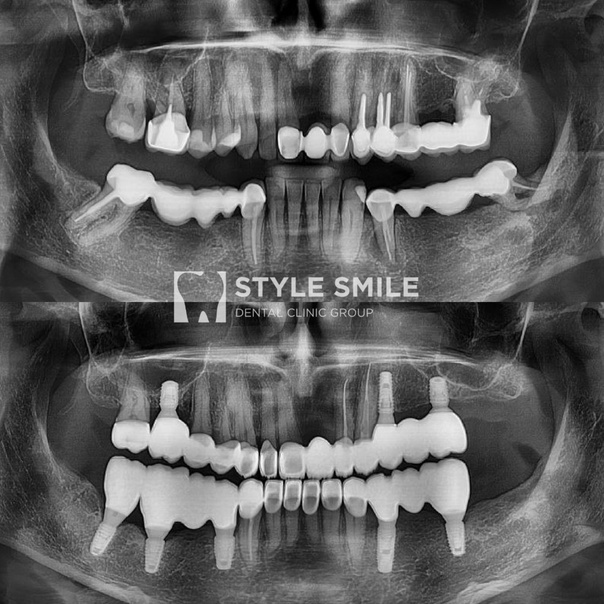

Тотальная реконструкция улыбки и нормализация основных пропорций лица

В данном случае, собрав анамнез, мы узнали, что пациентка не раз уже перепротезировалась, но никогда протезирование не было тотальным. При каждой замене конструкций терялась высота прикуса, что влияло на пропорции лица в целом. Со временем нижняя треть стала уступать средней трети лица.

Проведя тотальную реконструкцию прикуса, мы решили массу проблем. Спасли оставшиеся зубы и выполнили имплантацию, уходя от костных посадок, а также разработали новую окклюзионную карту, имея уже определённые входные параметры, с которыми мы просто должны были считаться.

Результат нас более чем радует! Пациентка приобрела не только красивую улыбку, но и преобразилась внешне из-за нормализации основных пропорций лица.